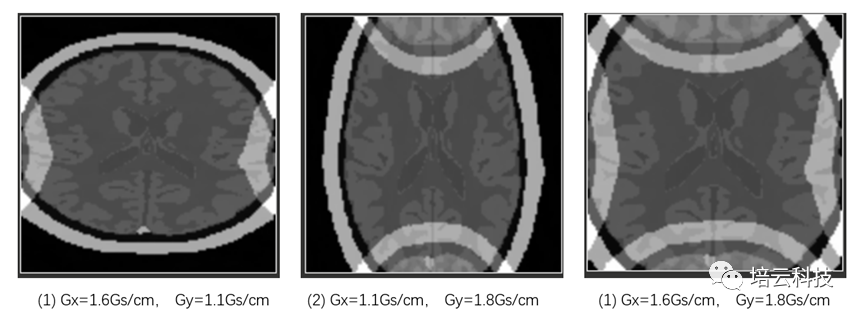

当采样带宽SW保持不变,分别调整三种梯度时:①Gx=1.6Gs/cm;②Gy=1.8Gs/cm;③Gx=1.6Gs/cm,Gy=1.8Gs/cm时,模拟采集得到的图像如图3所示,分别出现横向、纵向和横纵向的卷褶伪影。卷褶伪影出现的原因是,梯度过大,样品尺寸的左侧和右侧的自旋核产生的频率差,比决定视野范围的SW还要大时,超出的频率部分信号被卷褶到SW范围内了。根据频率和空间的映射关系,空间上也体现出图3所示的卷褶效果。

图3 不同的频率编码和相位编码梯度场下的卷褶伪影表现